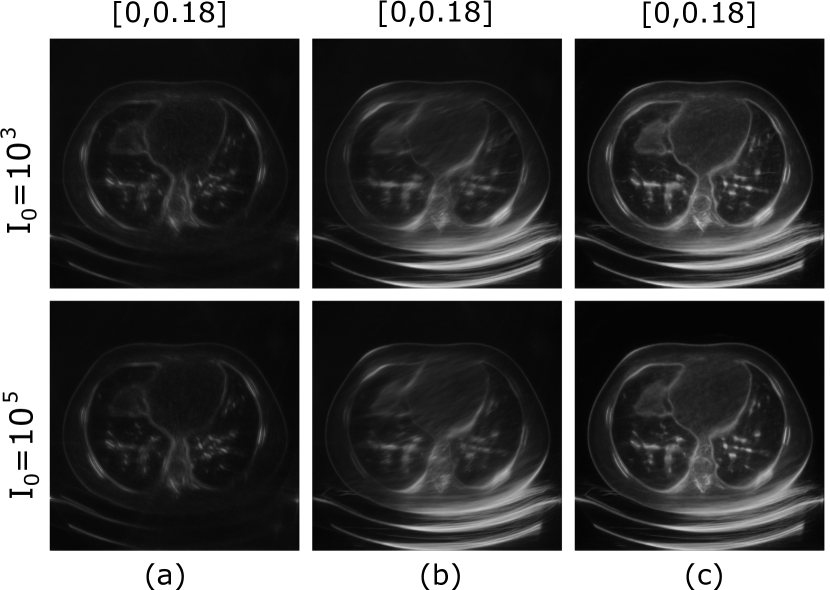

Samples of data-consistent alternate solutions obtained with the PULSE++ method using the same CT-StyleGAN model are shown in Fig. 9, corresponding to limited-angle projection data from Lung 1 (I0=103subscript𝐼0superscript103I_{0}=10^{3}, I0=105subscript𝐼0superscript105I_{0}=10^{5}) and Lung 2 (I0=103subscript𝐼0superscript103I_{0}=10^{3}). Additional alternate solutions are provided in the supplementary material described in the Appendix. The alternate solutions in each case displayed considerable variability in fine-scale structures. This illustrates the ability of the proposed PULSE++ method to produce diverse data-consistent solutions from the same measurement data for high-dimensional objects, which may be computationally infeasible with currently available posterior sampling methods.

Refer to caption

Figure 9: Alternate data-consistent solutions obtained using the PULSE++ method using the CT-StyleGAN model under different settings, for projection data from Lung 1 (I0=103subscript𝐼0superscript103I_{0}=10^{3}, I0=105subscript𝐼0superscript105I_{0}=10^{5}) and Lung 2 (I0=103subscript𝐼0superscript103I_{0}=10^{3}). Zoomed-in images of the same region in the alternate solutions inside the red bounding box demonstrate diversity in a number of fine-scale structures. The grayscale range of the alternate solutions is [0,1].